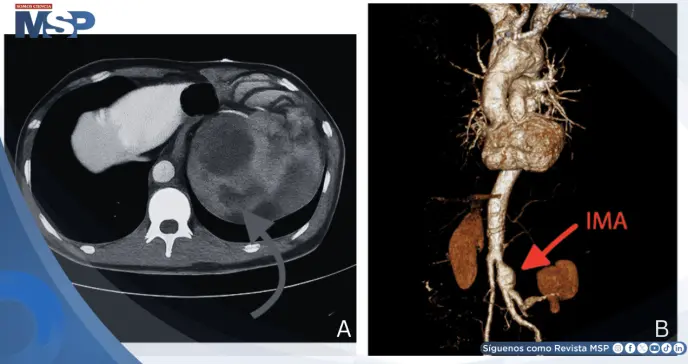

Se inició antibioticoterapia de amplio espectro y se solicitó tomografía computarizada abdomino-pélvica sin contraste para caracterizar mejor el proceso infeccioso sospechado. De manera inesperada, las imágenes revelaron un extenso hematoma retroperitoneal, hallazgo que motivó la realización urgente de angiografía por tomografía computarizada.

El estudio contrastado confirmó la presencia de un aneurisma de arteria mesentérica inferior roto asociado a disección aórtica abdominal.

El hematoma retroperitoneal ejercía efecto compresivo sobre el riñón izquierdo, explicando la hidronefrosis secundaria que inicialmente había orientado hacia un proceso infeccioso. No se identificaron abscesos renales ni infección parenquimatosa renal, descartándose definitivamente la hipótesis diagnóstica inicial.